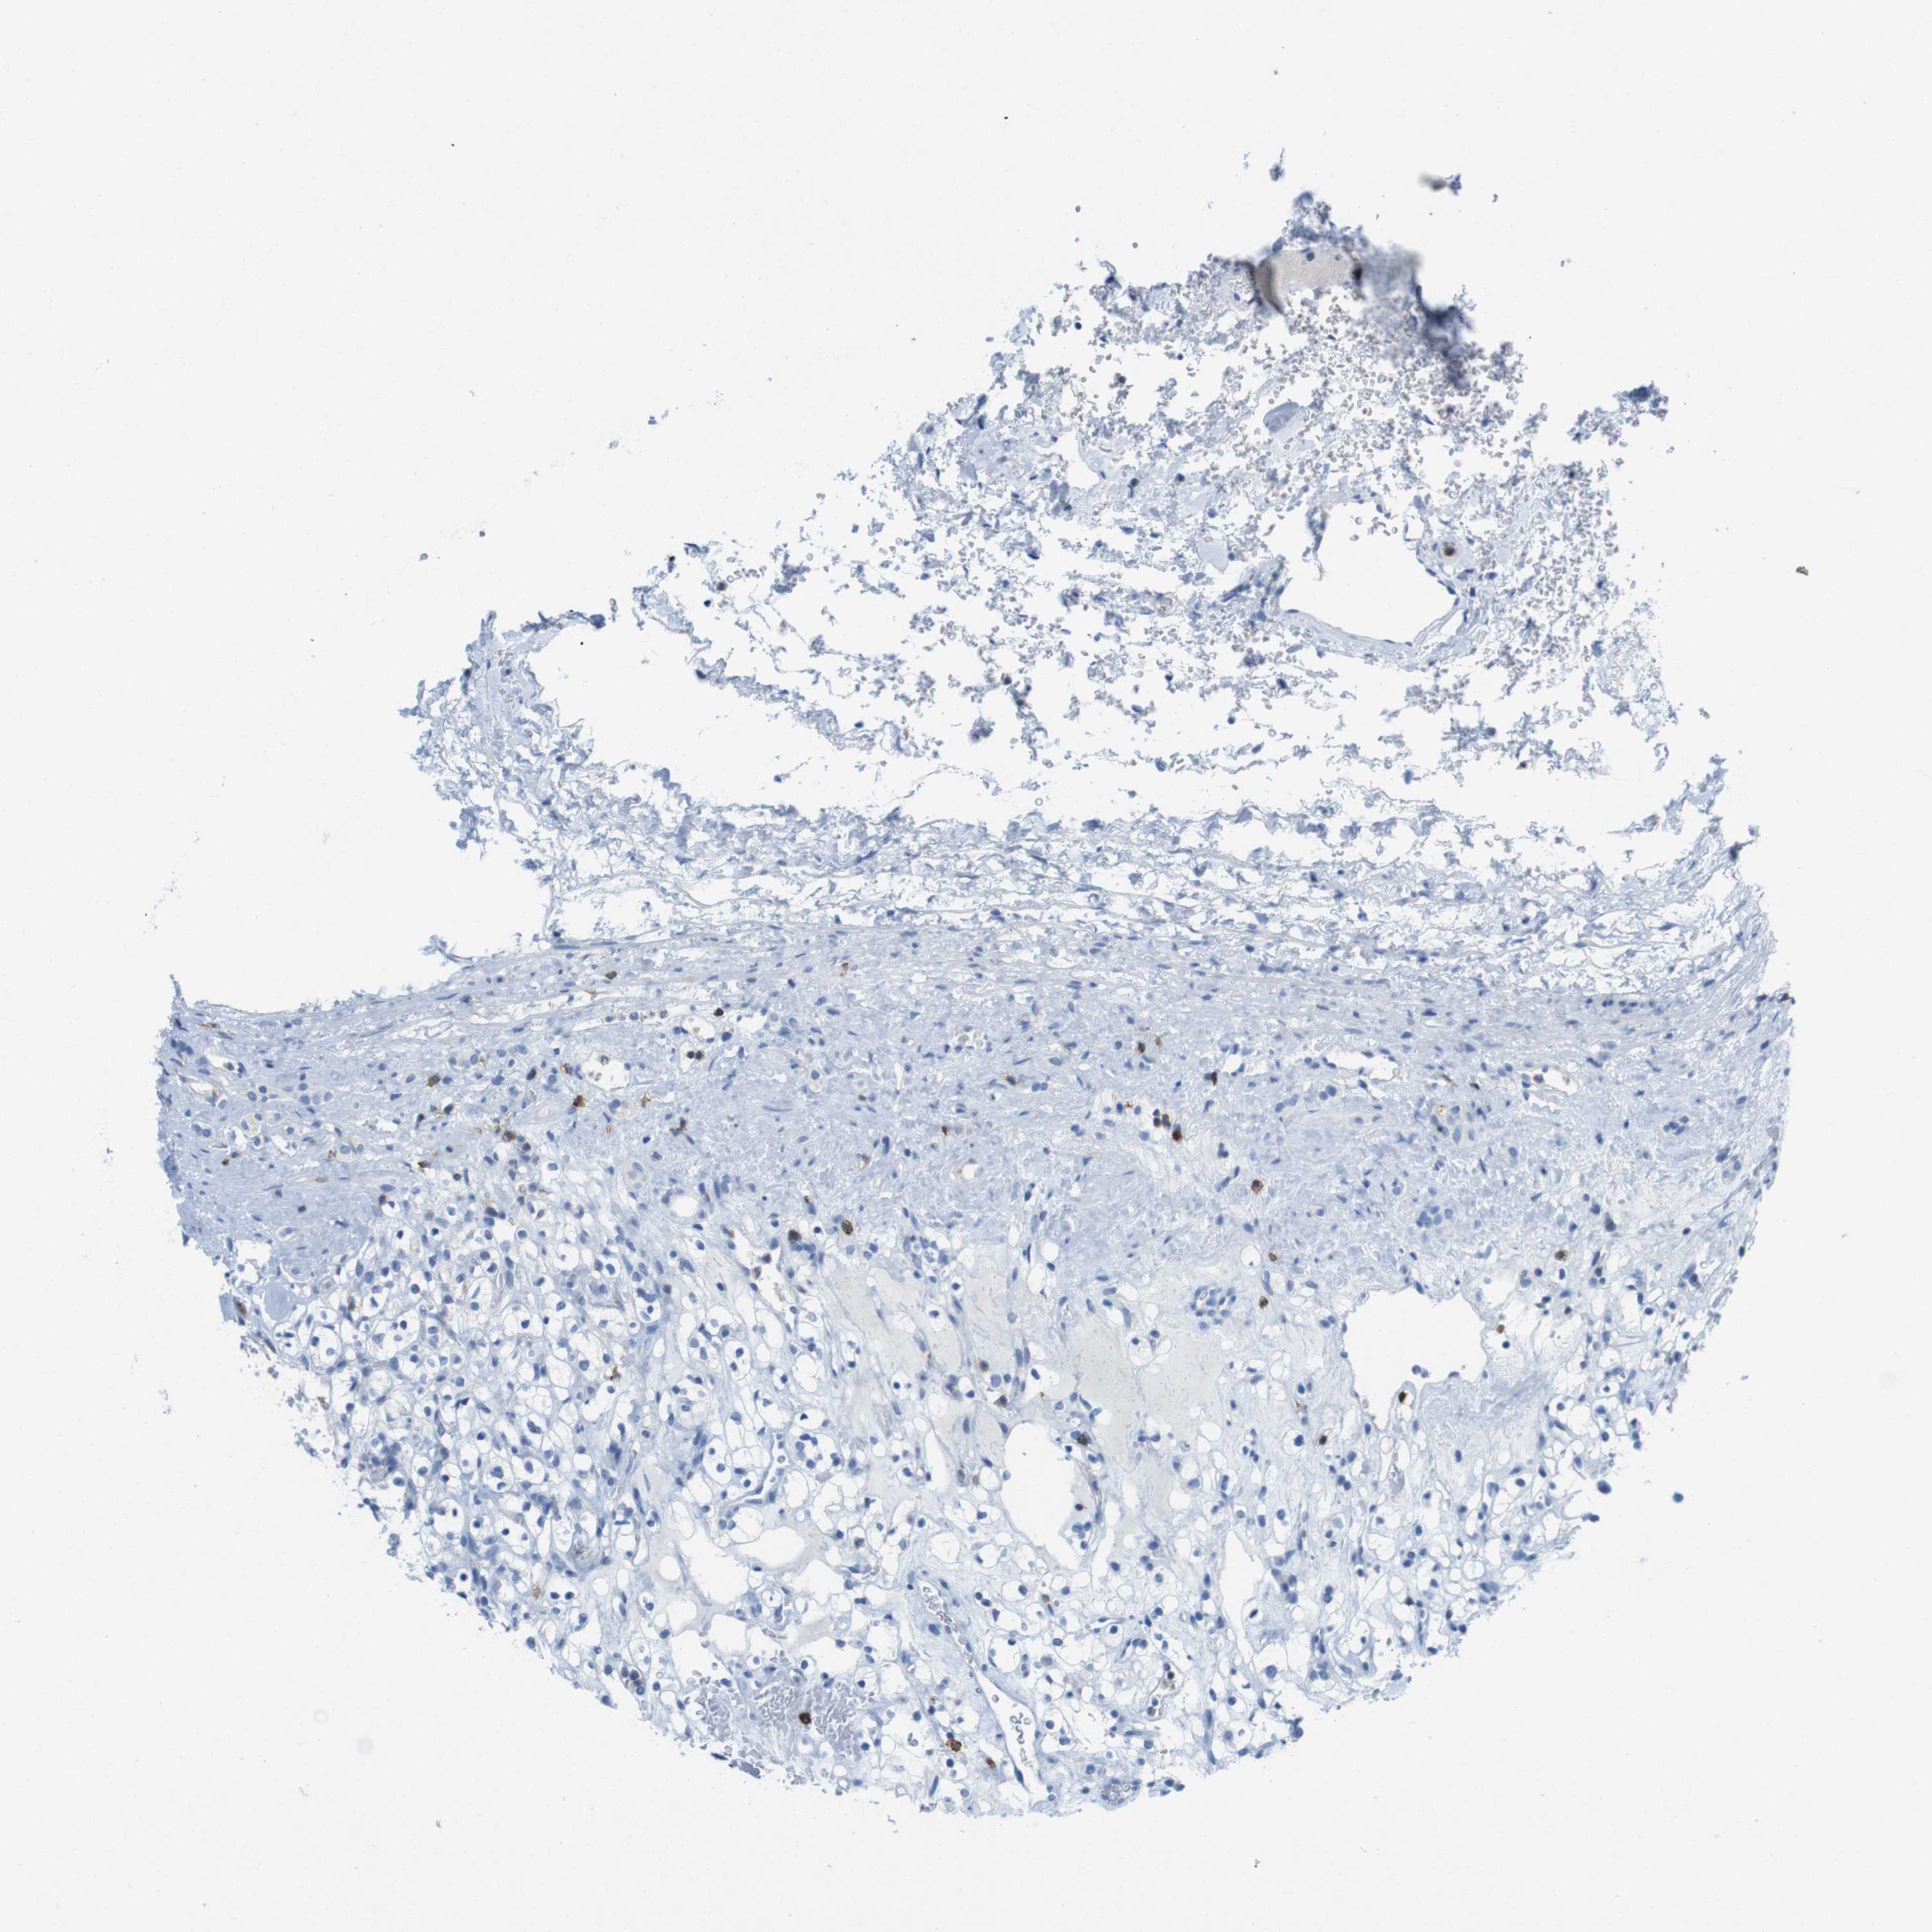

KIDNEY RENAL CLEAR CELL CARCINOMA (VALIDATION) - Interactive survival scatter ploti

CD5 is not prognostic in Kidney Renal Clear Cell Carcinoma (validation)

: 1.89

Average pTPM 4.7

Number of samples 100